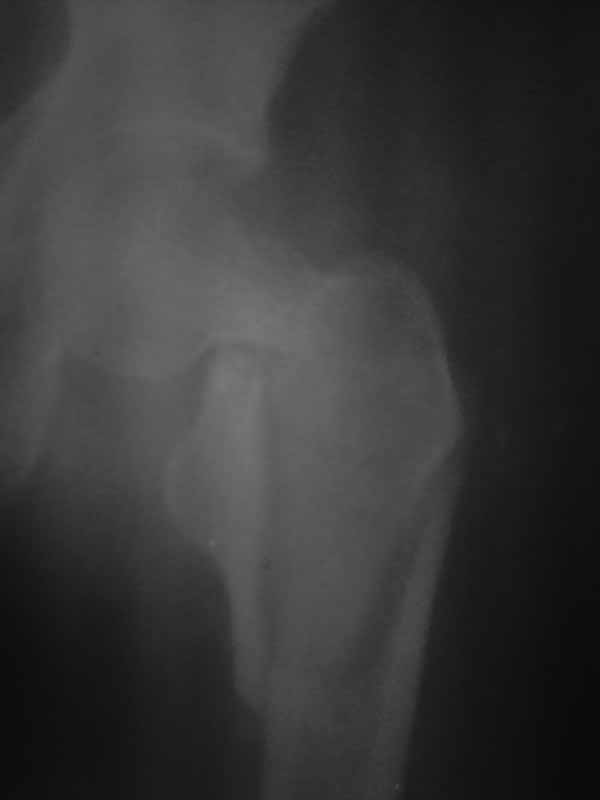

Хотелось услышать дискуссию, по-этому выложил некачественный снимок с вопросом. Стараюсь выложить немного лучше. Гамму она преобрести не сможет. Смущает то что шейка больно хлипкая и винтом развалим ее до конца. На снимке кажется что и фрагмент шейки также сломан вдоль.

Имя     : 4.jpg

Тип     : image/jpg

Размер  : 14140 байтов

Описание: отсутствует

Url     : http://weborto.net:8080/pipermail/ortho/attachments/20111002/91f177e3/attachment-0007.jpg